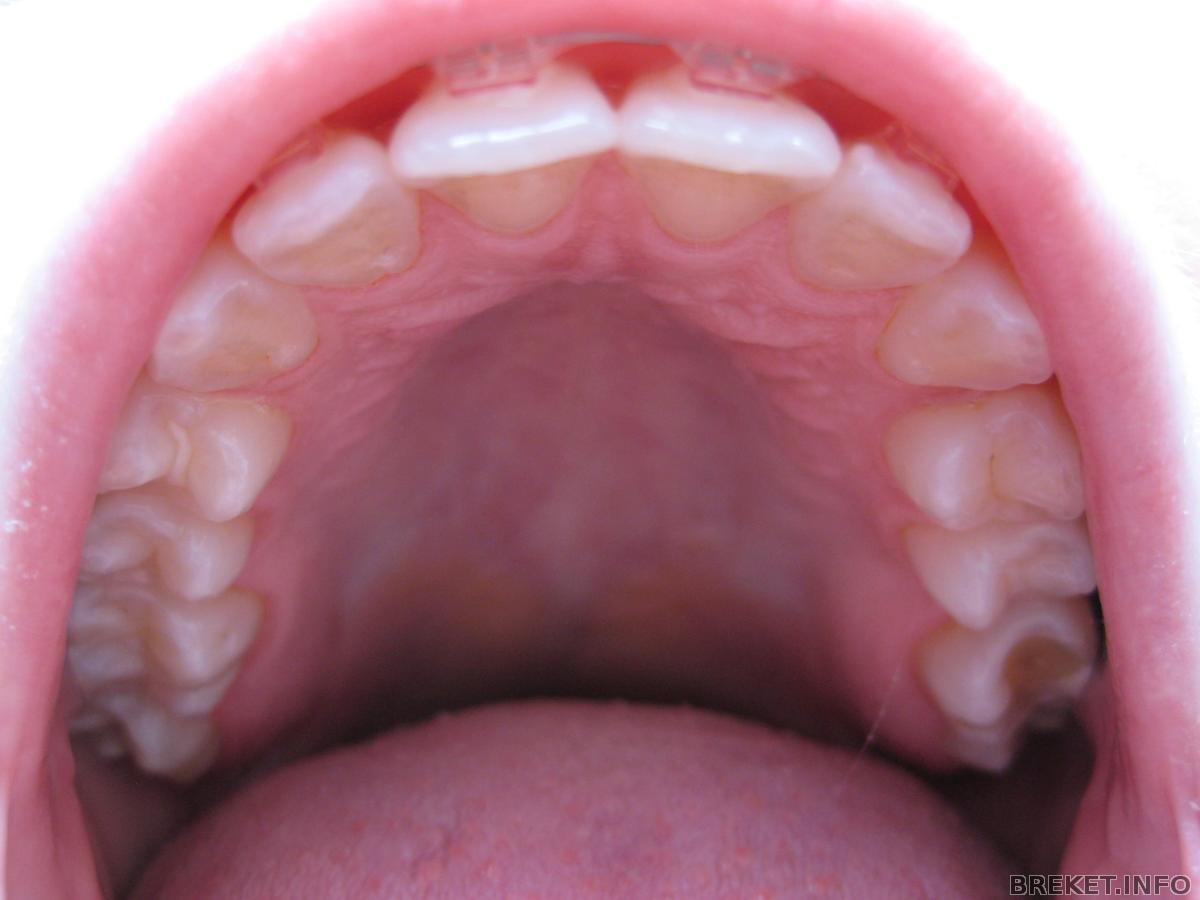

Была на приеме. Поменяли лигатурки, поставила прозрачные вместо розовых) Зубки выглядят по-другому сразу.

На ВЧ одели чейн почти на всю челюсть, потому что с одной стороны тоже небольшой промежуточек есть.